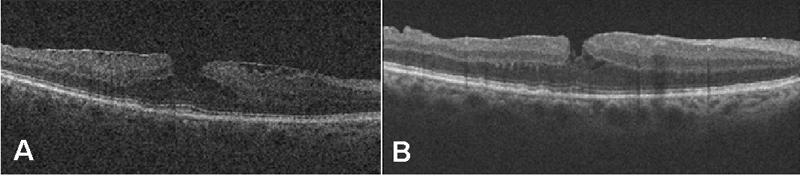

La sospecha diagnóstica de la CSC es eminentemente clínica, y suele confirmarse mediante angiografía fluoresceínica y OCT (

Figura 1). Recientemente, nuevos estudios con verde de indocianina y el desarrollo de nuevas OCT que permiten un mejor estudio de la coroides han relevado claves que hacen pensar en un origen coroideo de la enfermedad

Figura 1. Coroidorretinopatía serosa central aguda en ojo derecho. Se objetiva punto de fuga en la angiografía fluoresceínica y desprendimiento neurosensorial de la retina.

Formas agudas4,5

La tomografía en las formas agudas muestra un desprendimiento neurosensorial. A diferencia de otras enfermedades, como la degeneración macular, en la CSC suele existir una conservación parcial de la retina externa y del epitelio pigmentario, y se aprecia un alongamiento moderado de los segmentos externos de los fotorreceptores, la desaparición de la capa elipsoide, una disminución del grosor de la capa nuclear externa y normalidad en la membrana limitante externa (

Figura 2 y

Figura 3).

Figura 2. Hallazgos en la coroidorretinopatía serosa central aguda. Se aprecia un desprendimiento neurosensorial, con disminución de la capa nuclear externa. La membrana limitante externa aparece conservada. Existe un alargamiento de los fotorreceptores y una alteración de la capa elipsoide (flechas blancas).